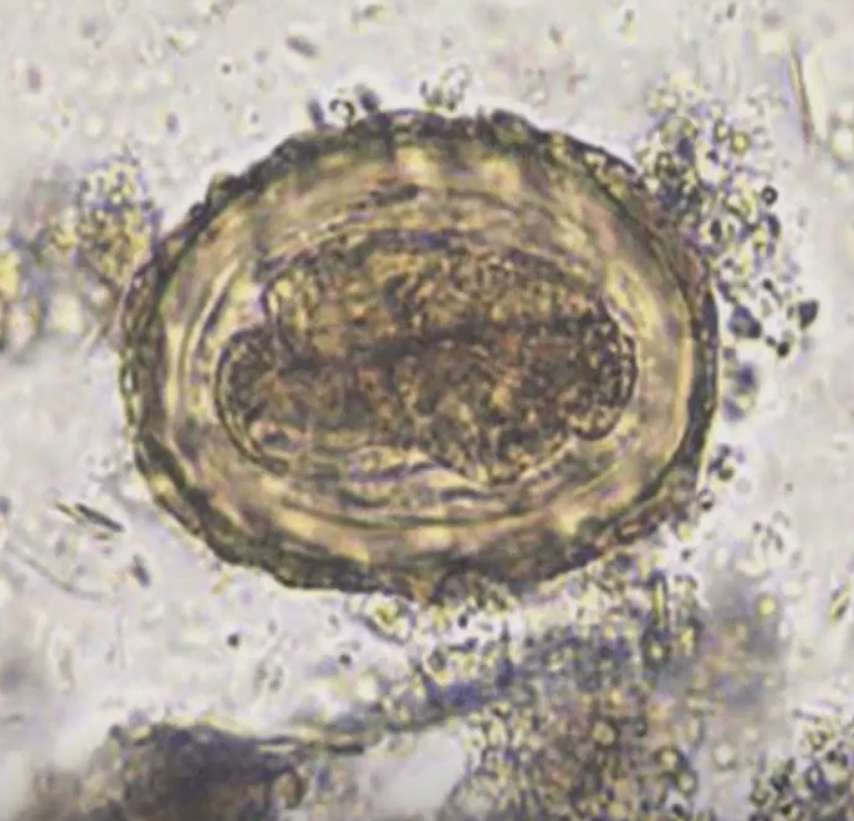

Trichuris trichiura ova parameter: fertilized: size

50-55 by 25 um

Trichuris trichiura ova parameter: fertilized: shape

barrel, foot-ball shaped,

hyaline bi-polar plugs

Trichuris trichiura ova parameter: fertilized: embryo

Unicellular; underdeveloped

Trichuris trichiura ova parameter: fertilized: shell:

Smooth yellow brown because of bile contact

T. trichiura eggs (measurement)

50-54 um by 23 um